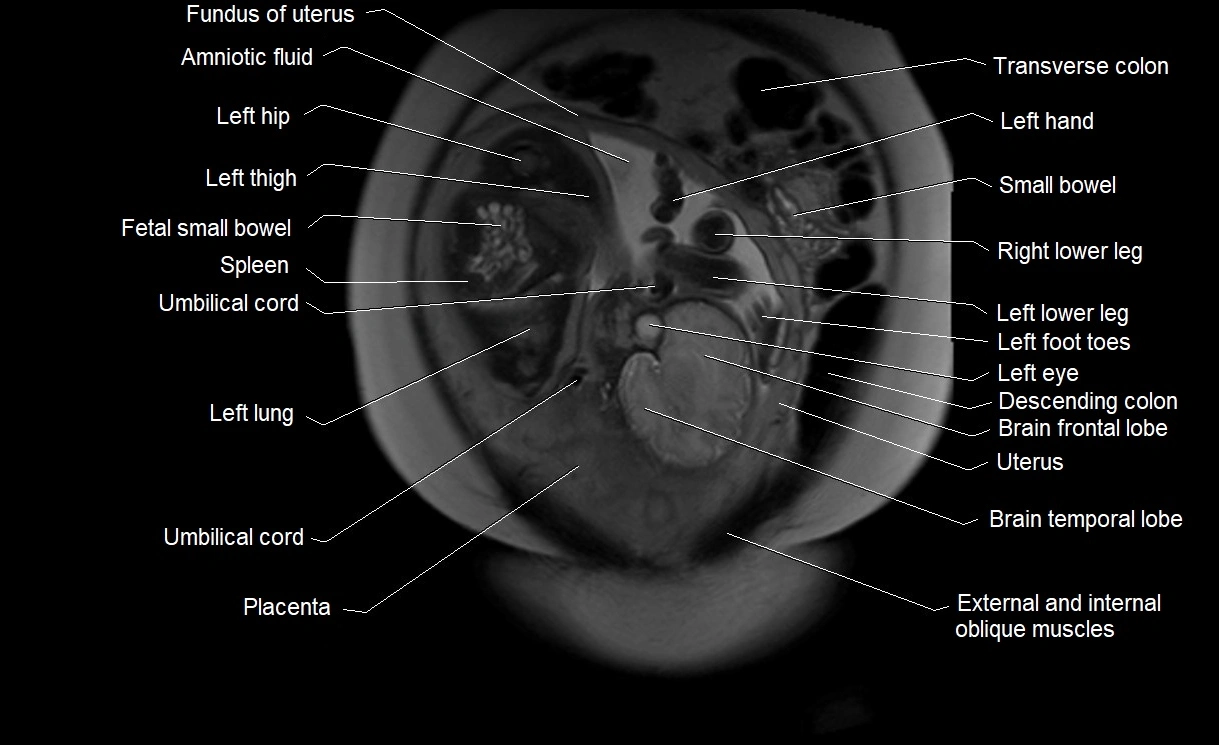

MRI Appearance

T2 HASTE (T2 GRE):

• Amniotic fluid shows very bright hyperintense signal

• Provides natural contrast against fetus and placenta

• Small particles (vernix) may appear as scattered hypointense foci within bright fluid

MRI image

image